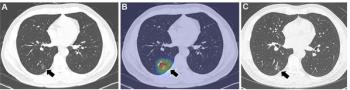

Emerging research shows that a multiple time-series deep learning model assessment of CT images provides 20 percent higher sensitivity than a delta radiomic model and 56 percent higher sensitivity than a clinical model for prognostic evaluation of ground-glass nodules.